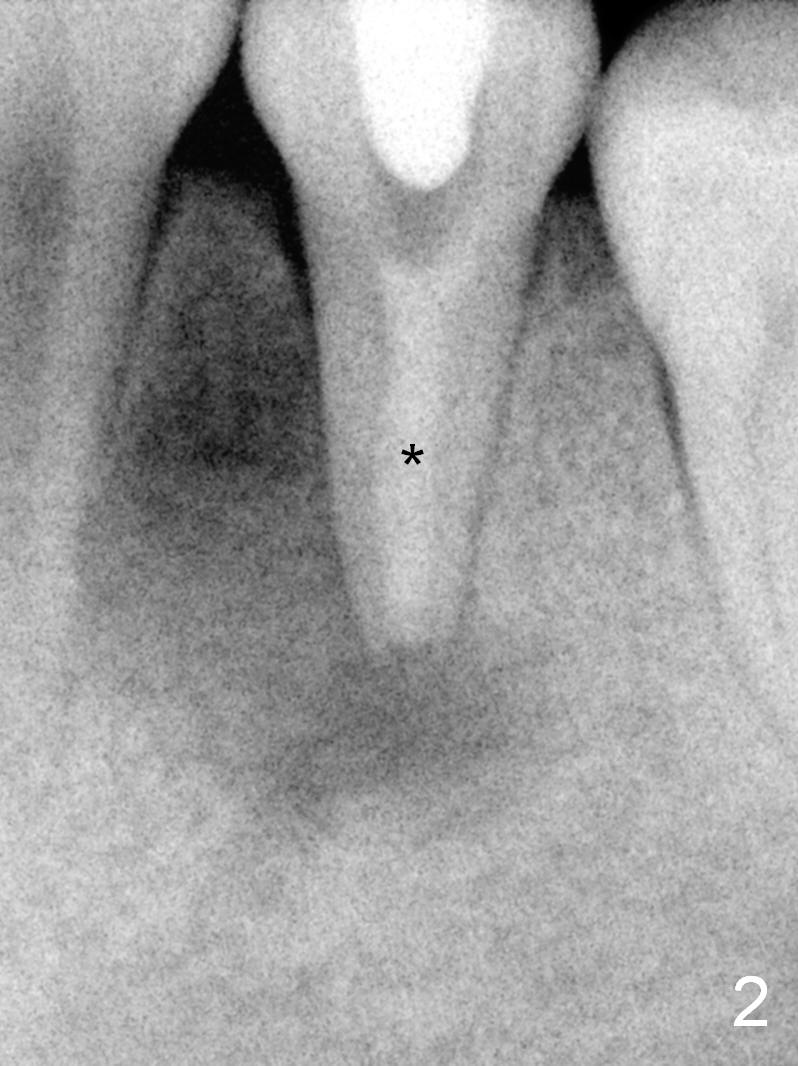

A 13-year-old girl has a buccal apical fistula at the tooth #20 with large periradicular radiolucency (Fig.1 *). After canal debridement, calcium hydroxide paste is placed in the canal (Fig.2 *). One month later, the fistula does not disappear with light percussion. New paste is placed (Fig.3). Two months later, the fistula disappears without percussion. The existing paste (Fig.4) is changed (Fig.5 (yellow: radiolucency; red: Inferior Alveolar Canal)). Another 2 months later, the fistula does not recur; as before, the paste density decreases, so does periradicular radiolucency (Fig.6). Root canal is packed (Fig.7). Six months postop, periradicular radiolucency continues to decrease, while the lamina dura at the apex is discontinuous (Fig.8 between arrowheads). Seven years postop, the lamina dura at the apex is seemingly intact (Fig.9). The patient remains asymptomatic at #20. In fact there is an acute infection at #29.